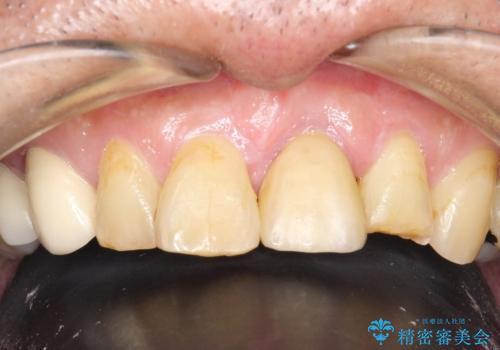

- 左の前歯で硬いものを咬んだら、歯からバキッと音がしてその衝撃で痛みが出た、その後前歯がゆれると来院されました。

左上1が水平的に割れている状態で、歯冠を取り除くと神経が露出しており、唇側はかなり歯肉縁下で破折しており、そのままではかぶせものを入れるのは難しい状態でした。

とても治療に対しての意識が高い方で、最初のころは歯磨きもあまりできていませんでしたが、衛生士さんの指導もあり、治療を進めるうちにプラークコントロールも改善していました。

歯を引っ張りあげたり、手術をしたあとの治り待ちをしたり、治療に時間がかかる方法ではありましたが、抜かずにその歯を使うことができたことで、患者さんにはとても満足していただけています。